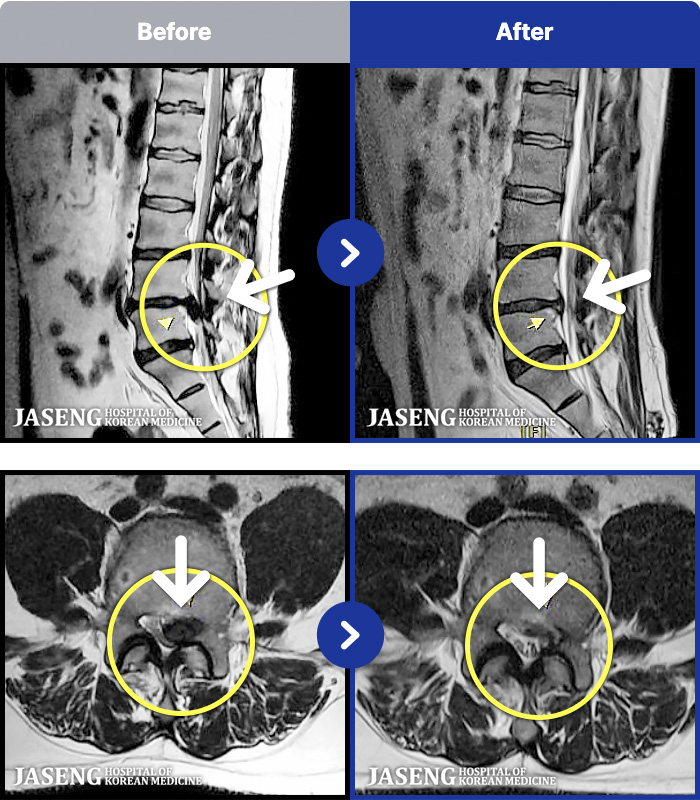

MRI ġ

94 MRI ũ ʸ Ȯϼ.